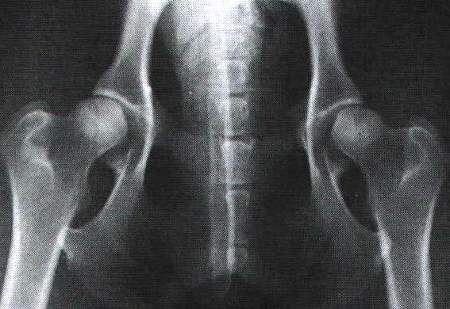

Röntgenaufnahmen zur HD-Beurteilung beim Hund

a- normal: Der Winkel sollte 105 Grad und mehr aufweisen

a- fast normal: Der Winkel sollte mindestens 100 Grad aufweisen

a- noch zugelassen: der Winkel zeigt ca. 100 Grad

mittlere HD: Die Winkelung liegt zwischen 90 bis 100 Grad

schwere HD: Die Winkelung liegt unter 90 Grad